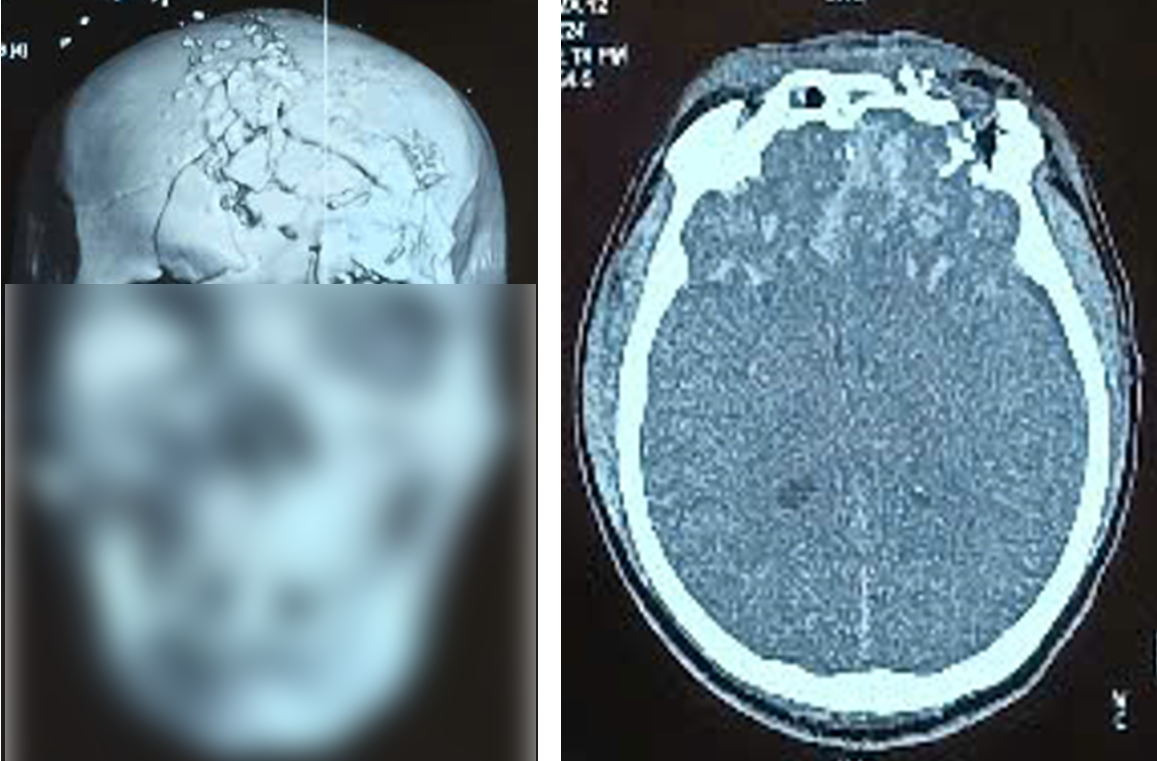

Bệnh nhân được chẩn đoán hôn mê, chấn thương sọ não hở: dập não vùng trán hai bên, vỡ xương vùng trán hai bên - đỉnh phải, vỡ xương phức tạp vùng hàm mặt, vỡ xương đá phải, bỏng độ II -III vùng mặt, bỏng độ II hai mắt.

Bệnh nhân đã được phẫu thuật cấp cứu mở xương sọ vùng trán hai bên giải ép não, lấy dị vật, khâu vết thương phần mềm.

Hình ảnh phim Cắt lớp vi tính xương sọ cho thấy xương sọ bị dập nát và tổn thương não khi bệnh nhân nhập viện. Ảnh BVCC

Sau mổ, bệnh nhân được hồi sức tích cực tại khoa Hồi sức Thần kinh. Bằng sự nỗ lực của các bác sĩ và nhân viên y tế, hiện tại bệnh nhân đã qua cơn nguy kịch, ổn định và đang tiếp tục được theo dõi, điều trị.

Tuy nhiên, tổn thương di chứng thần kinh nặng nề về nhận thức ý thức, liệt vận động, đặc biệt với tổn thương về mắt dẫn đến thị lực của bệnh nhân đã mất vĩnh viễn, cùng với các tổn thương vùng hàm mặt gây di chứng mất thẩm mỹ nặng nề.